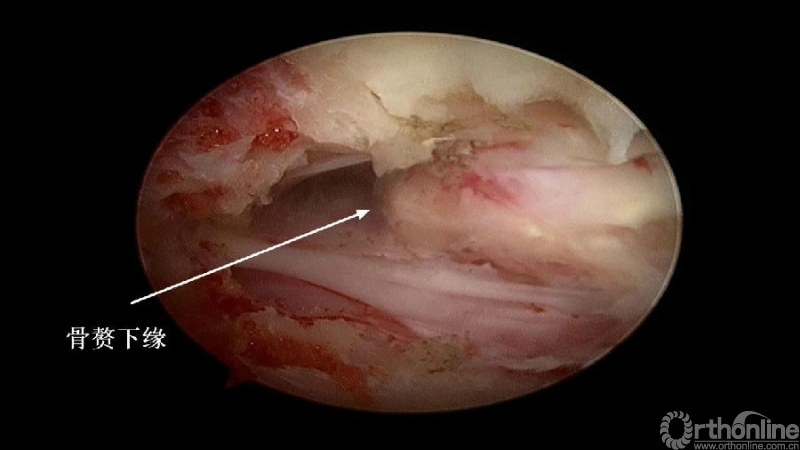

入院查体患者四肢肌张力高,双侧hoffman阳性。CT及MRI检查提示C4/5左侧关节突内缘有一巨大骨块(15mm*16mm),相应节段椎管严重狭窄。椎管内骨块的前端还有一游离骨块。

2. 术中骨赘的界限?